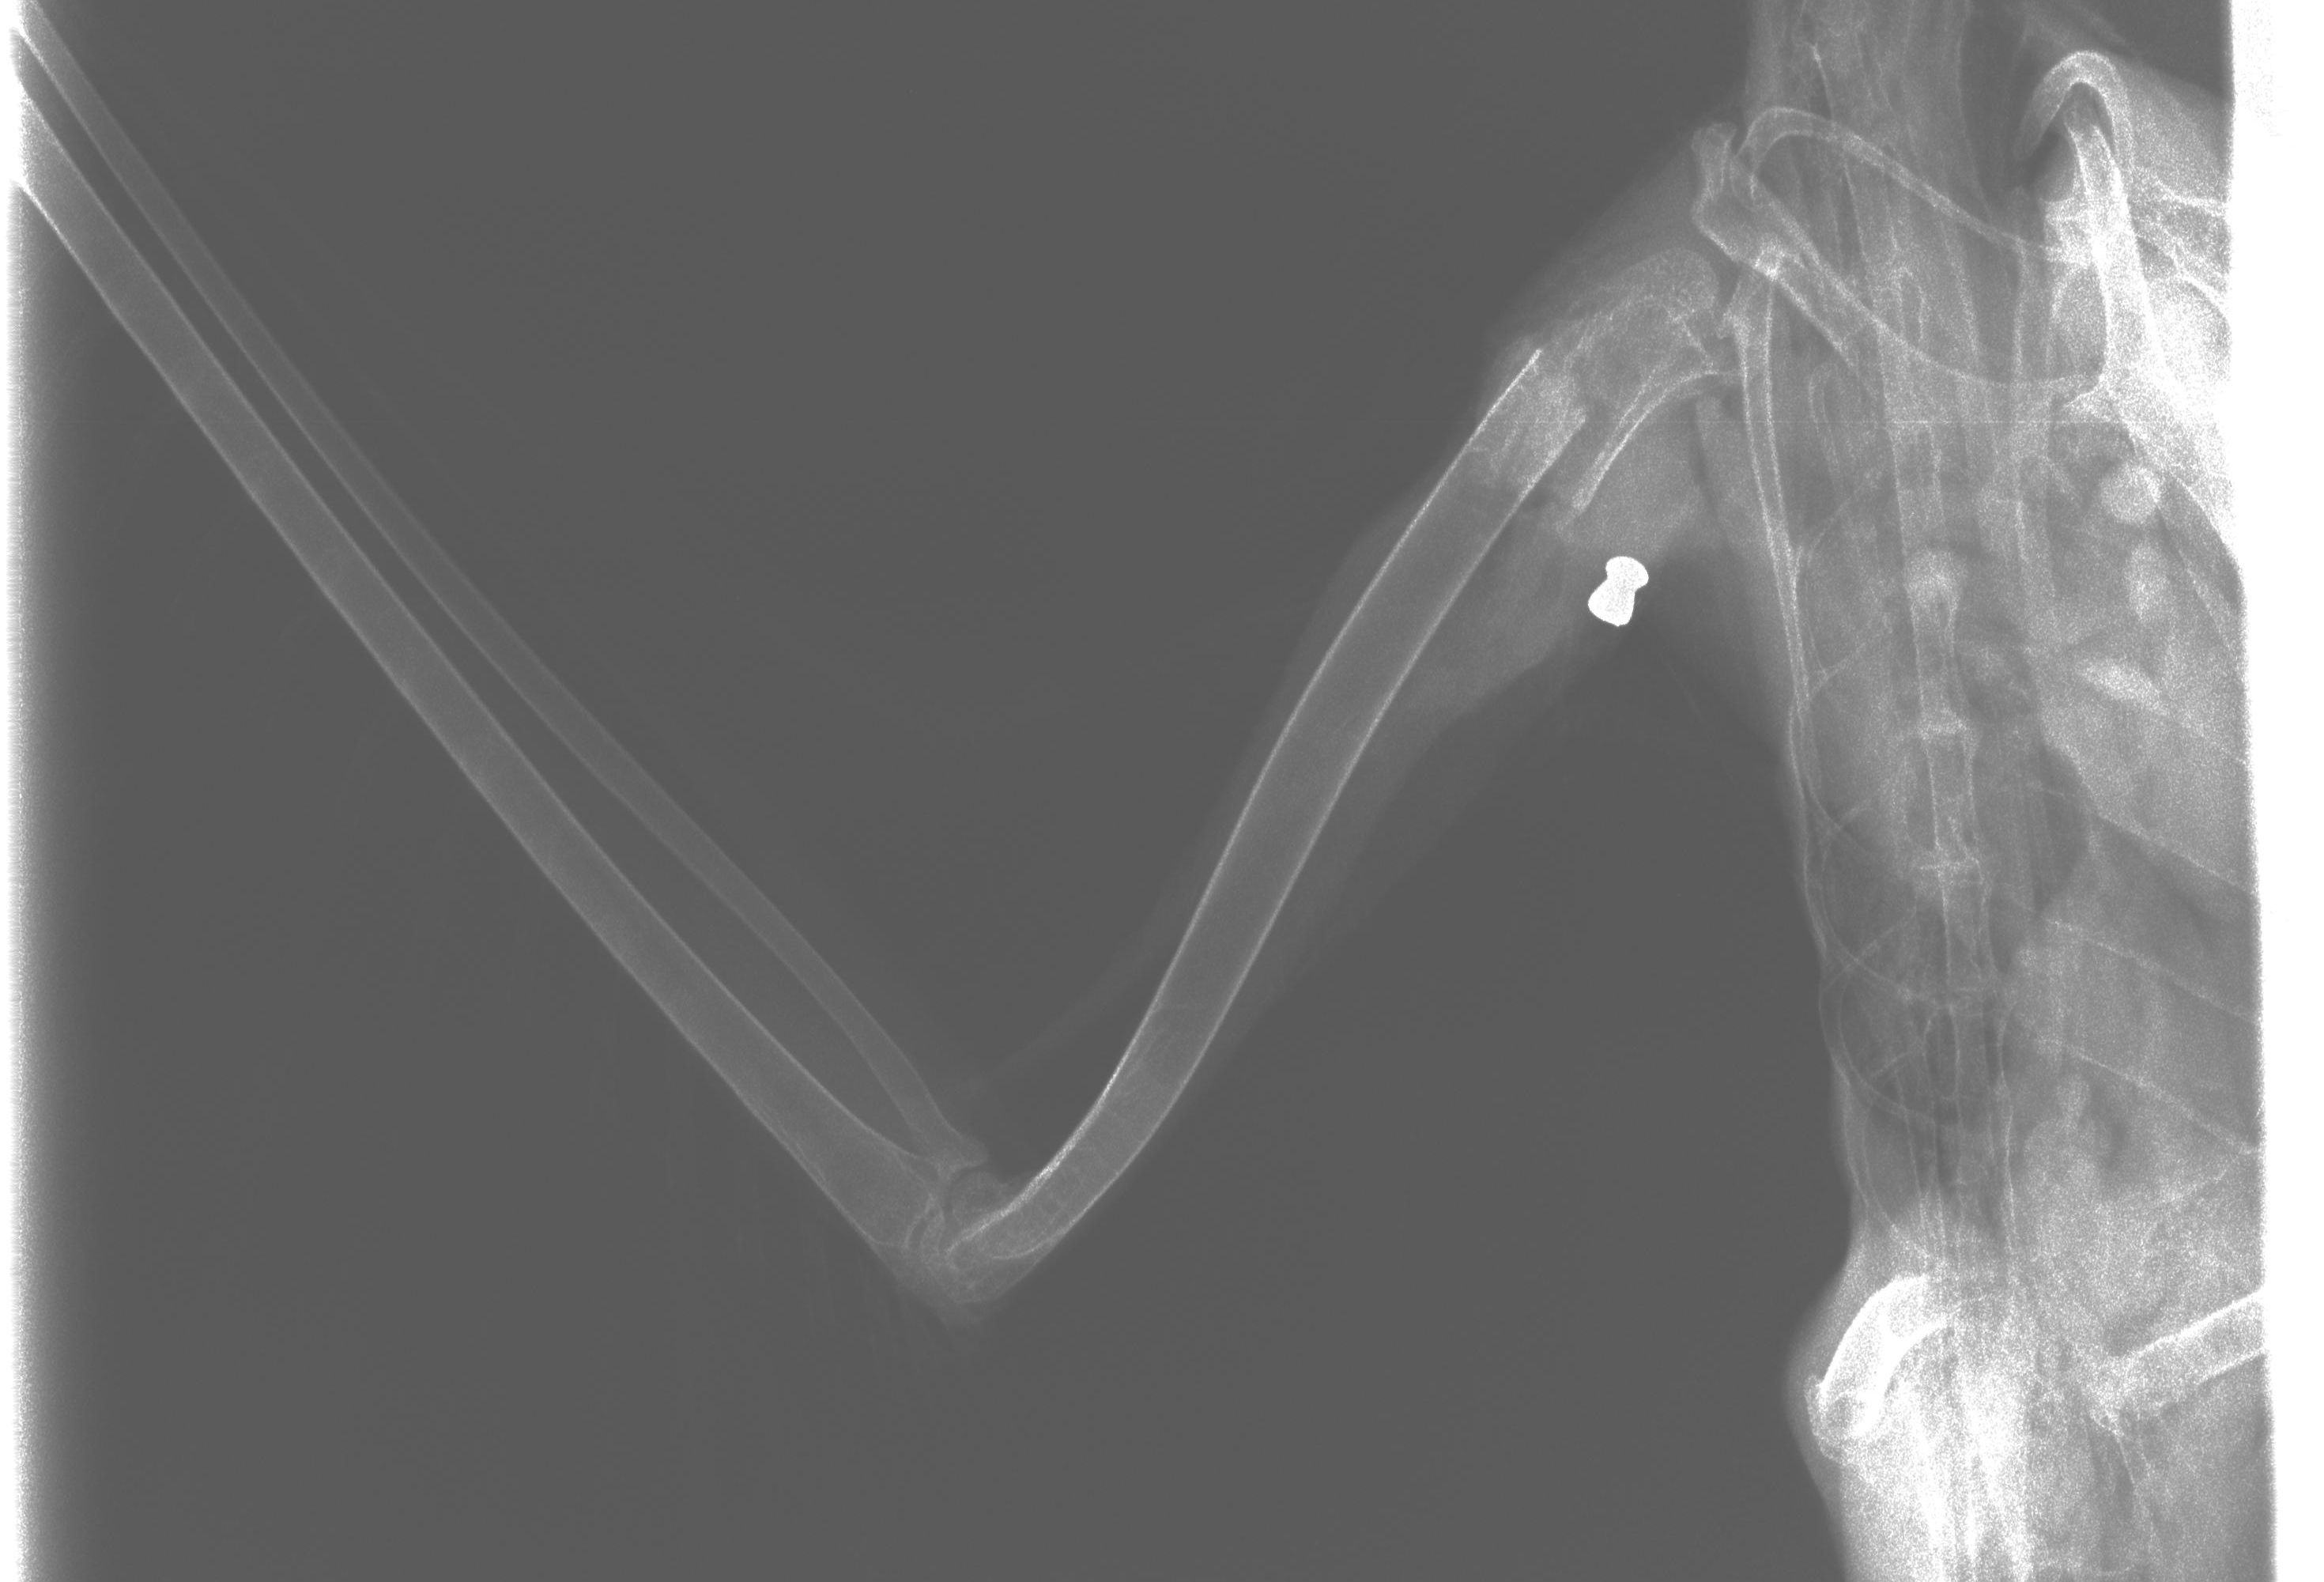

Bereits beim Fund war eine schwere Verletzung des Vogels an einem Flügel erkennbar gewesen. Im Rahmen einer Untersuchung wurde dann im Schultergelenk das Projektil eines Luftdruckgewehrs gefunden. "Aufgrund der Schwere der Verletzung konnte der Flügel nicht amputiert werden und das Tier musste leider euthanasiert werden", hieß es in der Aussendung.